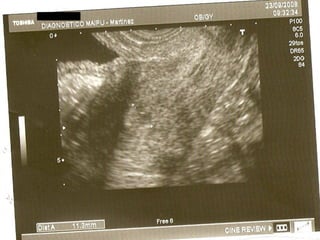

La ecografía ginecológica transrrectal es una ecografía endocavitaria que usa la vía transrrectal en lugar de la transvaginal. Se indica principalmente para pacientes vírgenes con ecografías ginecológicas no concluyentes, pacientes con vaginismo severo o hipotrofia marcada del introito y vagina. La técnica es similar a la ecografía transvaginal pero sin el tope vaginal, y permite imágenes casi idénticas.